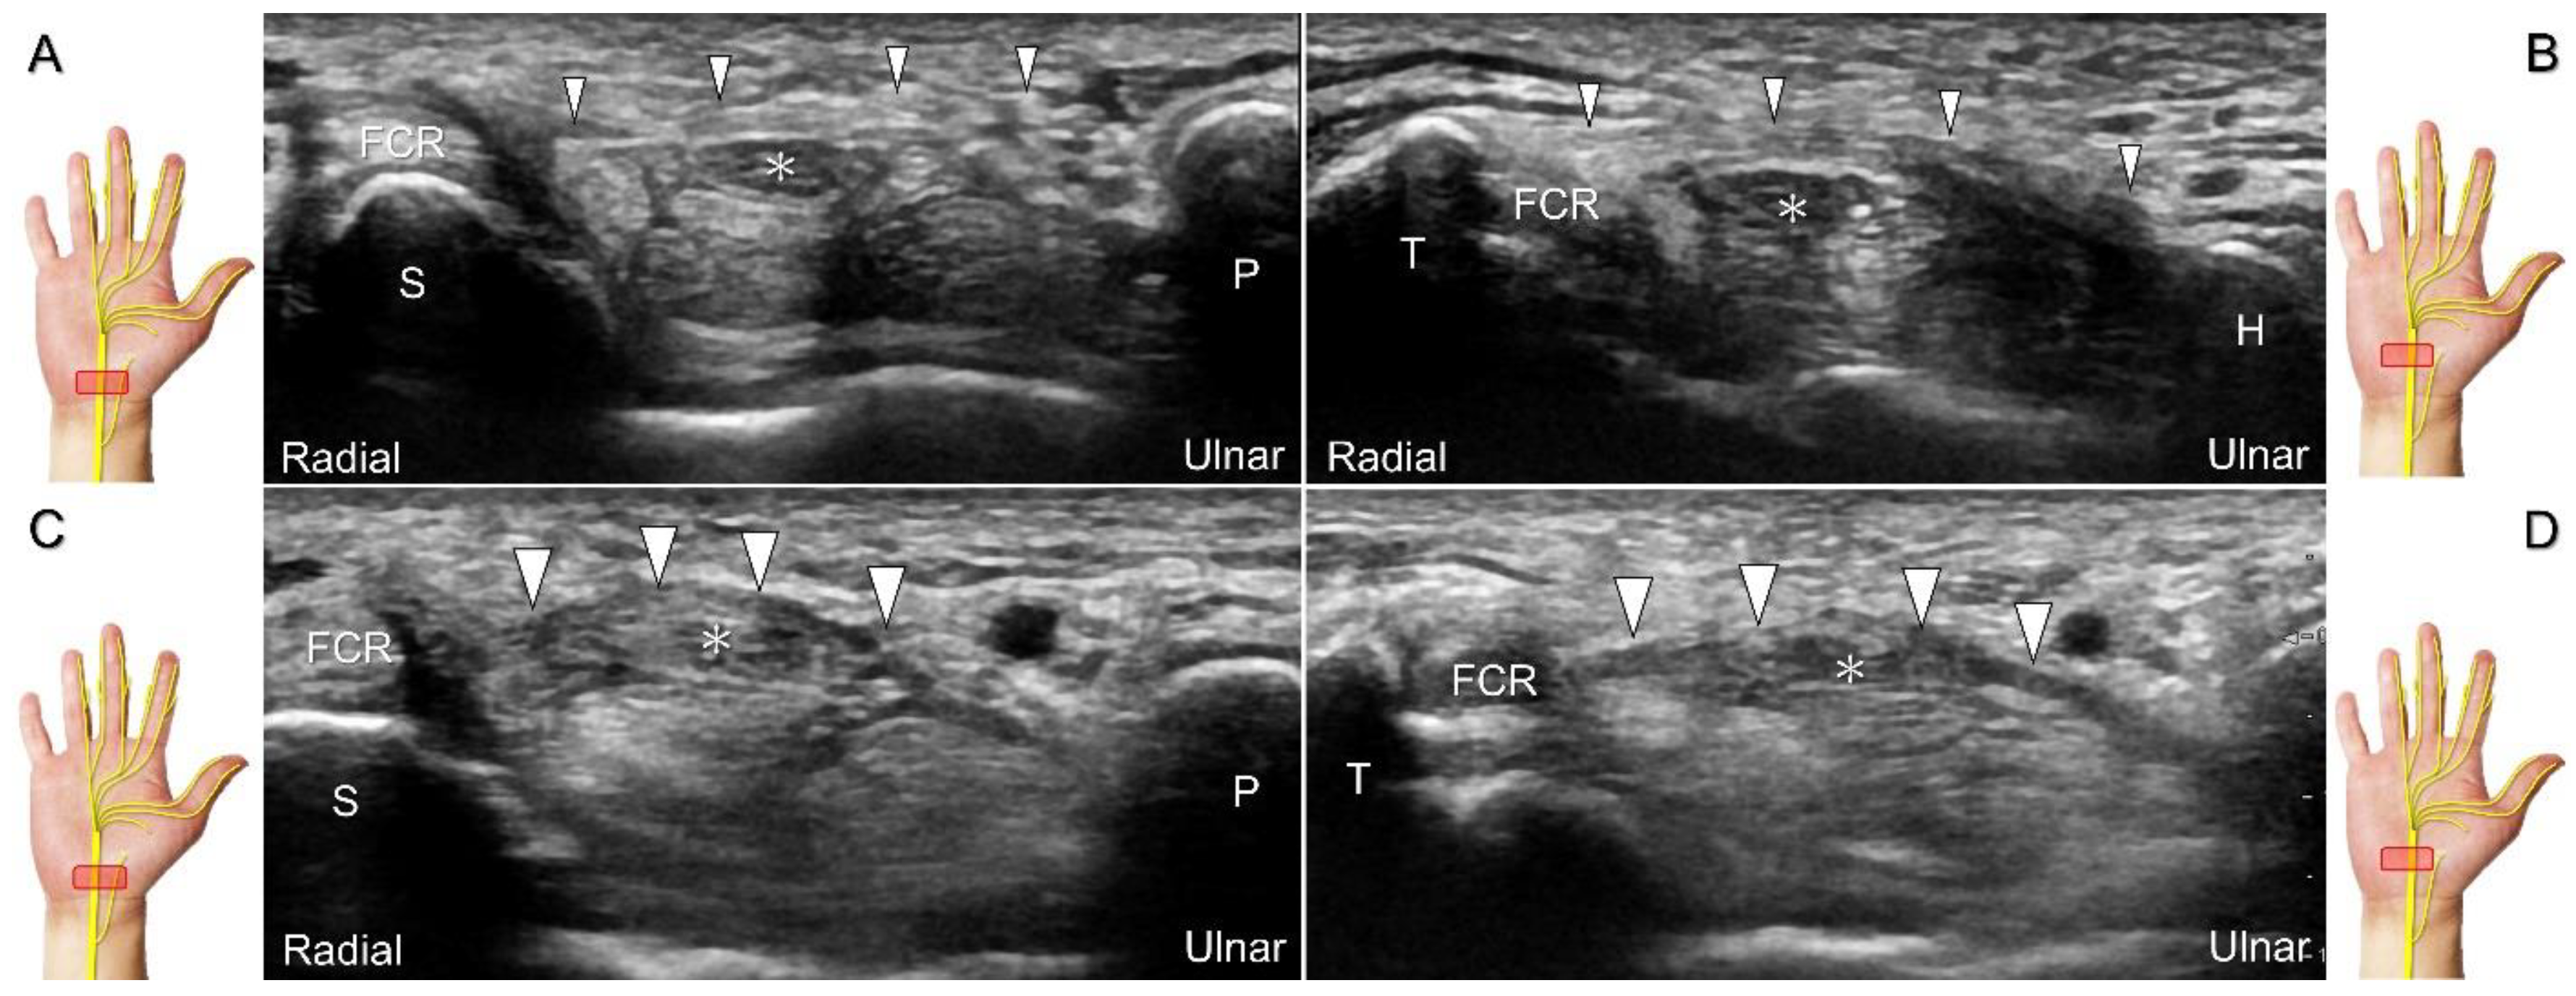

The transducer can be placed in the axial plane on the distal one-third of the forearm with the forearm supinated. The median nerve travels between the flexor digitorum superficialis and flexor digitorum profundus muscles. It gradually runs superficially to enter the carpal tunnel. The carpal tunnel inlet is defined as the plane crossing the scaphoid and pisiform (Figure 2A), whereas the plane linking the trapezium and hook of the hamate serves as the carpal tunnel outlet (Figure 2B).

Clinical Implication

Carpal tunnel syndrome is the most common entrapment neuropathy whereby the median nerve is entrapped by various causes, like hypertrophy of the flexor retinaculum (Figure 2C,D) and compression from the accessory muscles, swollen tendons, ganglions, and bony fractures within the tunnel. Ultrasonographic changes encompass swelling proximal to the entrapment site (Figure 3A), flattening over the entrapment site (Figure 3B), intraneural hypervascularity (Figure 3C), and focal loss of the trimline pattern (Figure 3D).

Figure 2. Sonographic/normal imaging of the median nerve from the inlet (A) to the outlet (B) of the carpal tunnel. Hypertrophy of the flexor retinaculum at both the inlet (C) and outlet (D) of the carpal tunnel. Asterisk: median nerve; small white arrowheads: normal flexor retinaculum; large arrowheads: hypertrophy of the flexor retinaculum. FCR: flexor carpi radialis; S: scaphoid; P: pisiform; T: trapezium; H: hook of the hamate.